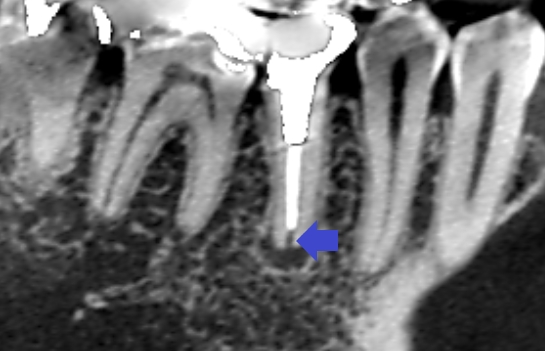

初診時のCT画像です。

根管充填が根の先まで足りず、細菌が繁殖できる空間ができているために膿んでいる可能性があります(青い矢印の先)。